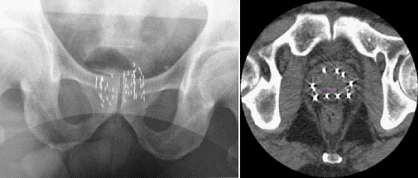

PSA値や直腸診、経直腸的前立腺超音波検査によってがんが疑われる場合、確定診断をするためには、前立腺の組織を採取する前立腺生検を行い、がん細胞の有無を病理学的に診断します。前述の経直腸的前立腺超音波検査で前立腺内部を観察しながら、バイオプティガンという自動生検装置を用いて、細い針で前立腺を刺して組織を採取します。

以前は6か所生検が一般的でしたが、最近のガイドラインで初回10か所以上の生検が推奨されており、当院でも前立腺の大きさを考慮しながら、10か所以上の生検を行うようにしています。採取された組織の病理検査を行い最終的な診断が行われます。

前立腺生検の経路(方法)には経直腸的と経会陰的(肛門と陰嚢の間から)行う方法とがあります。一般的には簡便な方法である経直腸的が多く行われていますが、経会陰的にくらべて直腸出血や急性前立腺炎などの合併症のリスクが若干高いため、通常は入院で行われています。また麻酔も局所麻酔で行う方法と下半身麻酔で行う方法がありますが、下半身麻酔の場合には通常入院で行われます。

当院では、外来で、安全かつ安心して行える方法として局所麻酔で経会陰生検をおこなっています。検査は麻酔を含めて約30分程度で終了します。